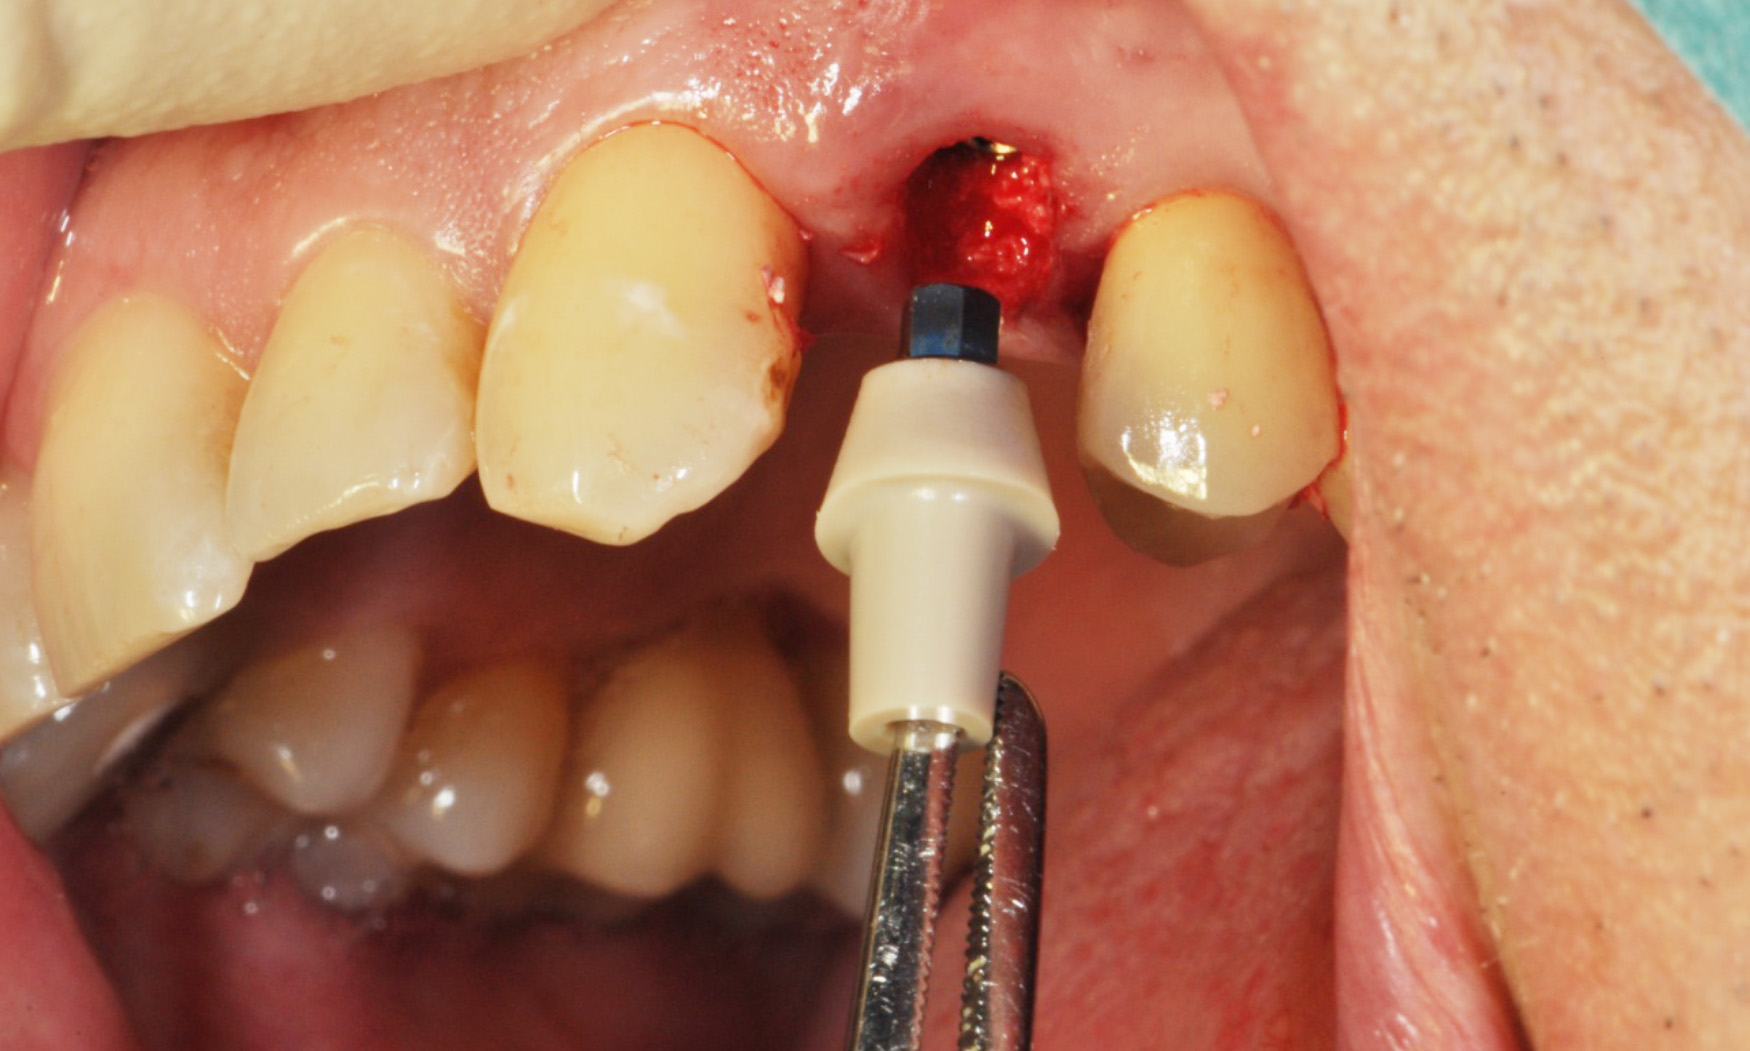

P2F – Use of an Anatomically Shaped Abutment with Immediate Implantation

Contributed by Dr. Frank Spiegelberg on Sep 08 2014

Short Summary: The following case shows immediate implant placement: surgical steps for successful preserving the soft and hard tissue by using an anatomically shaped gingiva former. The atraumatic...